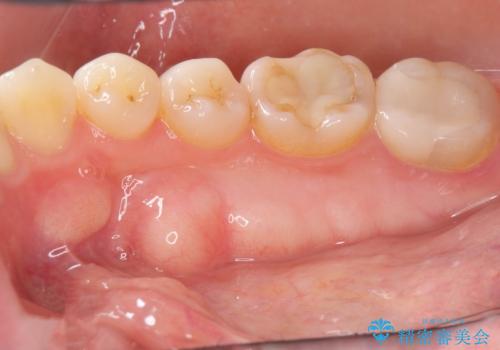

- 白い歯を主訴に来院されました。

元の色味がグレー系統の歯でした。

ホワイトニングエクセレントコース3回照射の施術をしました。